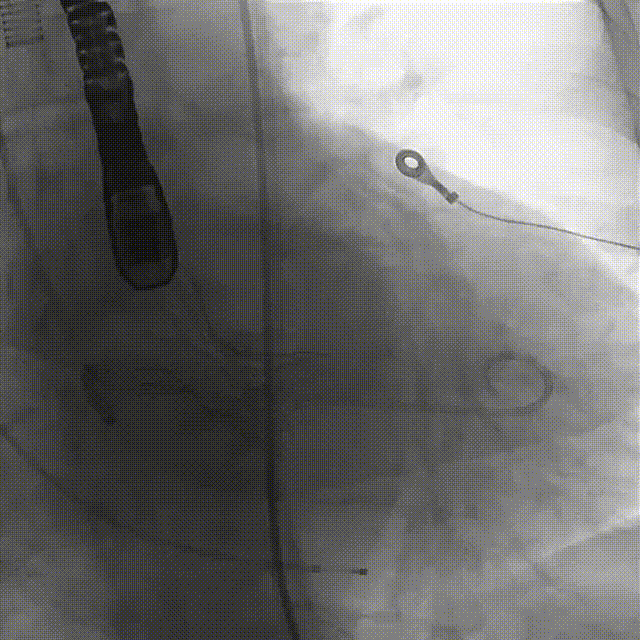

5.根据术前评估及球囊预扩情况,选择23mm沛嘉TaurusElite瓣膜进行植入,抓捕器辅助下输送器头端进入左室,零位定位

6.在150次/分快速起搏下释放瓣膜至工作位

7.瓣膜释放至工作位后造影示左右冠灌注尚可,瓣膜形态尚可,决定予以释放

(2)由于患者升主动脉严重扩张,血管并发症风险较高,术中提前将抓捕器备于瓣膜输送系统上,直接于抓捕器辅助下送入瓣膜。得益于良好的控制,基本未使器械与扩张的血管壁接触,极大减少了血管并发症风险。